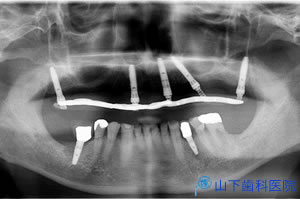

| 初診時上顎咬合面観 | ![]() |

| 初診時下顎咬合面観 治療は下顎から開始しました。銀歯を外し、根の治療状態に不安があれば再治療しました。 歯髄を失った根の治療は、最善を尽くしても、もともとの歯髄の再生、つまりは血の巡りを再建できないので治らないとお話しました。歯髄が生きている歯でないと長く持つ保証はできません。 血の巡りを失わらせた場での弱毒型常在菌バイオフィルム感染症は場ごと取り去らないかぎり治癒しない、免疫的排除が働かないために完治しない、この点では強毒型ウイルス感染症が激しい全身症状を引き起こして死亡することもあるが、治れば完治して免疫記憶に刻まれるのとは違う厄介さがあります。 根の中への再感染を防ぎ、歯髄を失ったために弱体化する歯質を補強するためには、接着歯学に基づいた土台建て(接着支台築造)を行うことが、現実にできる最善の策です。すべての土台をこの方法で建て直しました。 下顎の左右臼歯部の理想的な咬み合せ面を作るべく、割れないセラミックと言われているイットリウム安定化酸化ジルコニウムを素材にしたブリッジ、単独冠(クラウン)修復をドイツ人技工士が開発したZirkonzahn社のシステムの改良版で行いました。 |

![]() |